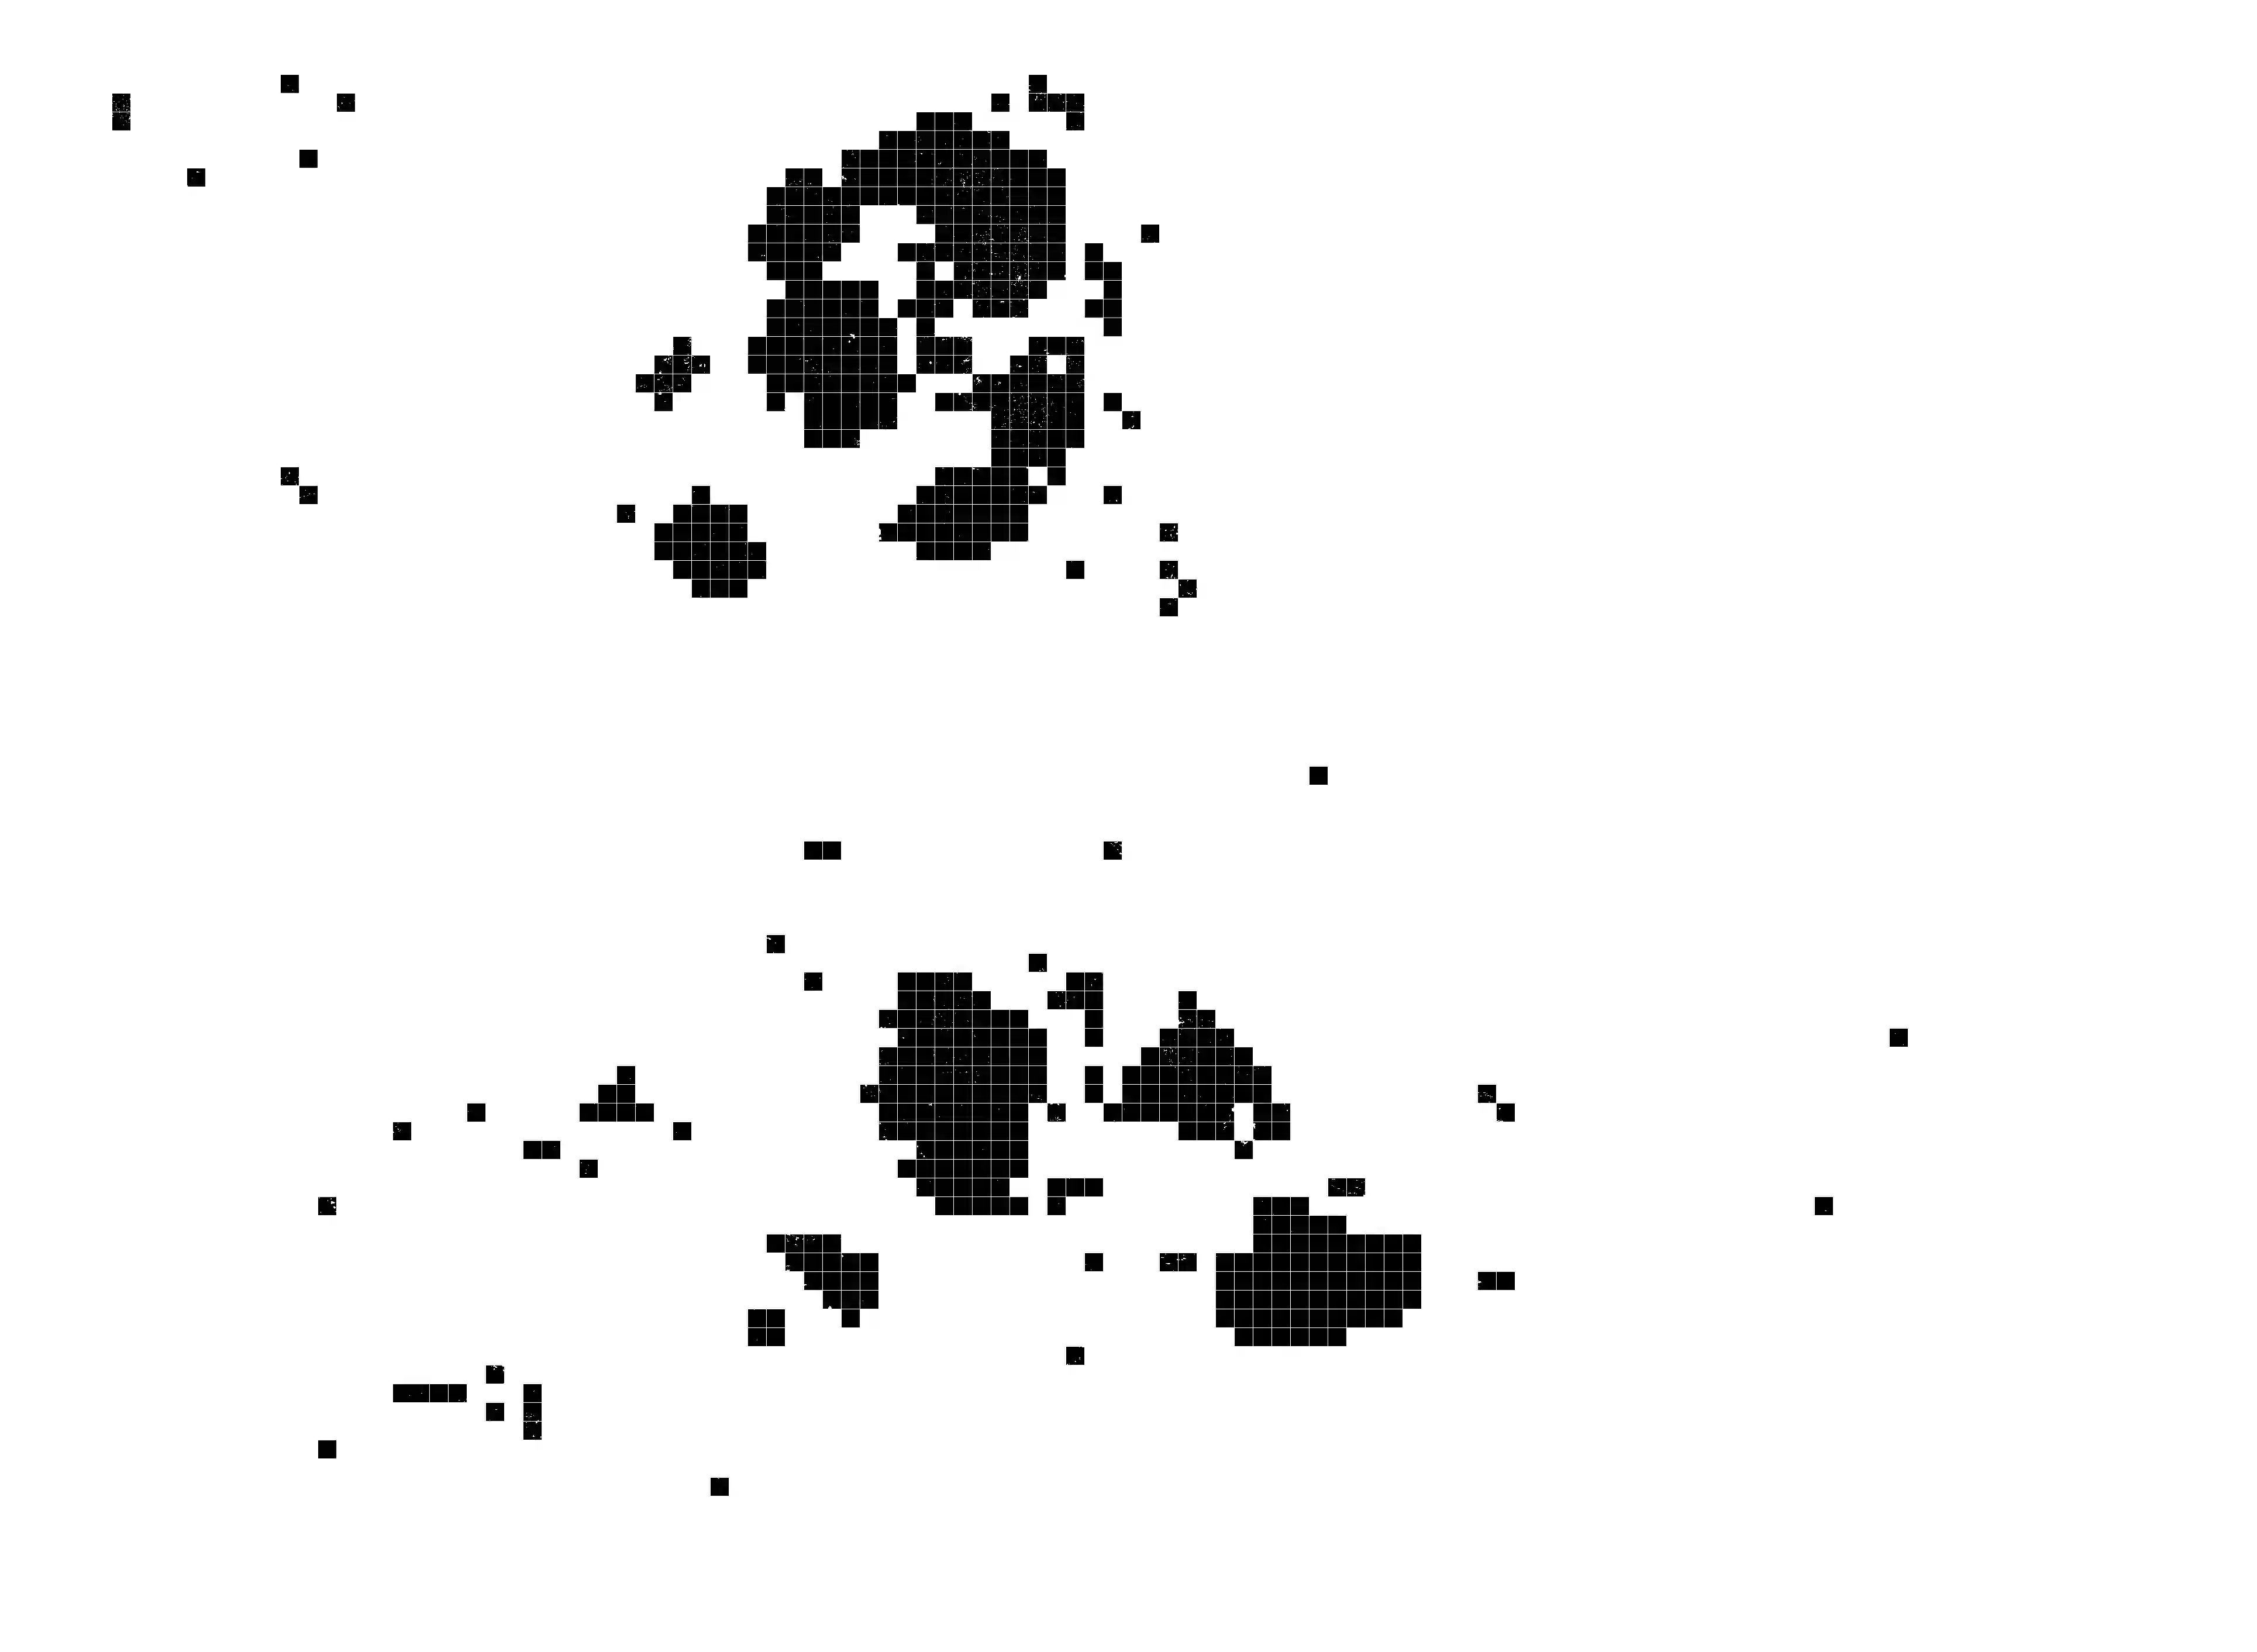

Whole slide images (WSIs) pose unique challenges when training deep learning models. They are very large which makes it necessary to break each image down into smaller patches for analysis, image features have to be extracted at multiple scales in order to capture both detail and context, and extreme class imbalances may exist. Significant progress has been made in the analysis of these images, thanks largely due to the availability of public annotated datasets. We postulate, however, that even if a method scores well on a challenge task, this success may not translate to good performance in a more clinically relevant workflow. Many datasets consist of image patches which may suffer from data curation bias; other datasets are only labelled at the whole slide level and the lack of annotations across an image may mask erroneous local predictions so long as the final decision is correct. In this paper, we outline the differences between patch or slide-level classification versus methods that need to localize or segment cancer accurately across the whole slide, and we experimentally verify that best practices differ in both cases. We apply a binary cancer detection network on post neoadjuvant therapy breast cancer WSIs to find the tumor bed outlining the extent of cancer, a task which requires sensitivity and precision across the whole slide. We extensively study multiple design choices and their effects on the outcome, including architectures and augmentations. Furthermore, we propose a negative data sampling strategy, which drastically reduces the false positive rate (7% on slide level) and improves each metric pertinent to our problem, with a 15% reduction in the error of tumor extent.